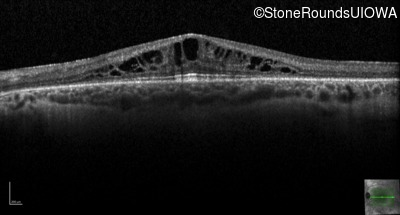

Retinitis Pigmentosa with Anemia (IB10)

OCT Stack

Retinitis Pigmentosa with Anemia

TRNT1

IVS5-26 T>C

Lys416 ins1tggA

AR